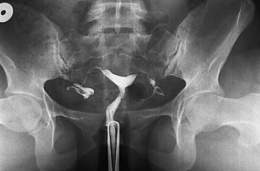

El útero arcuato es una variante del útero septado, pero el septo es mucho menos pronunciado en profundidad, aunque tiene una base más ancha. El útero arcuato generalmente no está relacionado con problemas de fertilidad ni presenta riesgo aumentado durante el embarazo.